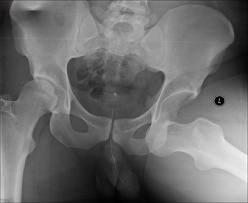

Femoral Neck Fractures

Hip dislocations &

femoral head fractures

Femoral neck fractures |